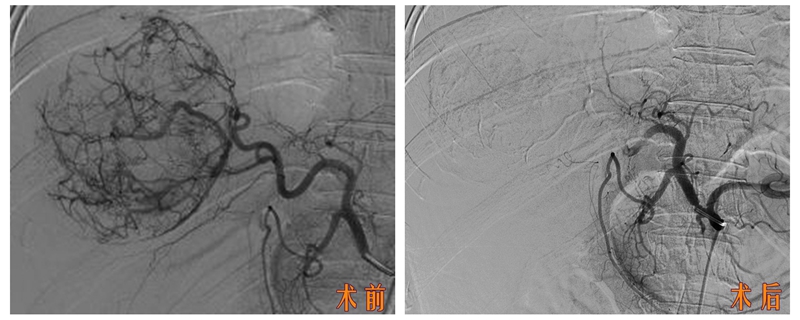

患者被送入导管室后,郑胜与放射科主治医师苏维杰第一时间开始经股动脉肝动脉造影与栓塞术。术中用碘化油及明胶海绵颗粒对出血动脉进行了栓塞,成功止血。

郑胜介绍,相较于急诊开腹止血手术,介入栓塞术具有创伤小、恢复快、并发症少等优势,能最大限度地保护肝功能。

同时,血管造影能进一步明确肿块大小、范围及血管情况,为接下来的治疗提供依据。

【介入栓塞术现场图】